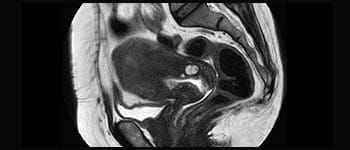

La Sra. Silvia Schiffer, directora y radióloga experta en la clínica Radiologie Schiffer, en Alemania, comparte sus experiencias con el sistema de RM Prodiva 1.5T.

Conozca la opinión de los primeros usuarios de Ingenia Prodiva 1.5T acerca de sus experiencias con el sistema y cómo influye este en su centro de diagnóstico por imagen.

Mayor fiabilidad diagnóstica en neurooncología